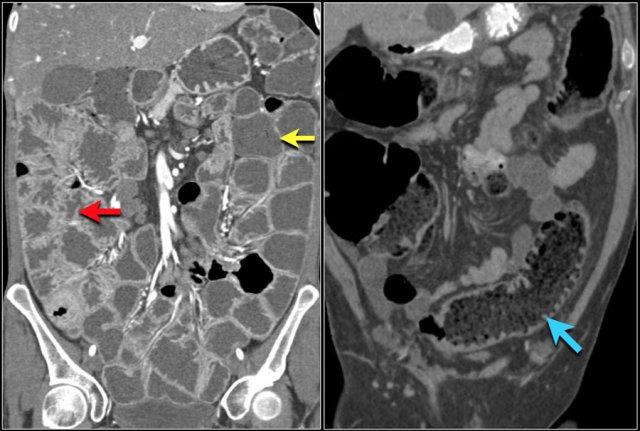

Đây là hình ảnh bệnh nhân thiếu máu cục bộ ruột do huyết khối tĩnh mạch mạc treo tràng trên – SMV (mũi tên đỏ).

Lưu ý tình trạng ứ máu tĩnh mạch trong mạc treo ruột (mũi tên vàng).

Đây là một bệnh nhân khác bị thiếu máu cục bộ một đoạn dài ruột non do tắc ruột quai kín.

Một đặc điểm hình ảnh quan trọng của tắc ruột quai kín là hình ảnh các quai ruột non giãn xếp theo kiểu nan hoa bánh xe với các mạch máu mạc treo hội tụ về một điểm trung tâm.

- Sự ngấm thuốc của thành ruột trong thiếu máu cục bộ có thể bình thường, tăng do hiện tượng tái tưới máu, hoặc giảm/mất ngấm thuốc như trong trường hợp này.

Đôi khi, tái tạo ảnh mặt phẳng coronal dạng lát cắt dày (thick slab coronal reconstructions) có thể hữu ích trong việc đánh giá mức độ ngấm thuốc.

Điều này được minh họa rõ ràng ở bệnh nhân này, trong đó hỗng tràng ngấm thuốc tốt (vùng xanh lá), trong khi hồi tràng giảm ngấm thuốc (vùng đỏ) do thiếu máu cục bộ.

Đây là một trường hợp tắc ruột quai kín khác.

Lưu ý sự khác biệt về mức độ ngấm thuốc giữa các quai ruột bình thường không giãn (mũi tên xanh lá) và các quai ruột giãn bị thắt nghẹt (mũi tên đỏ).

Ở trung tâm là các mạch máu mạc treo bị xoắn vặn (mũi tên vàng).